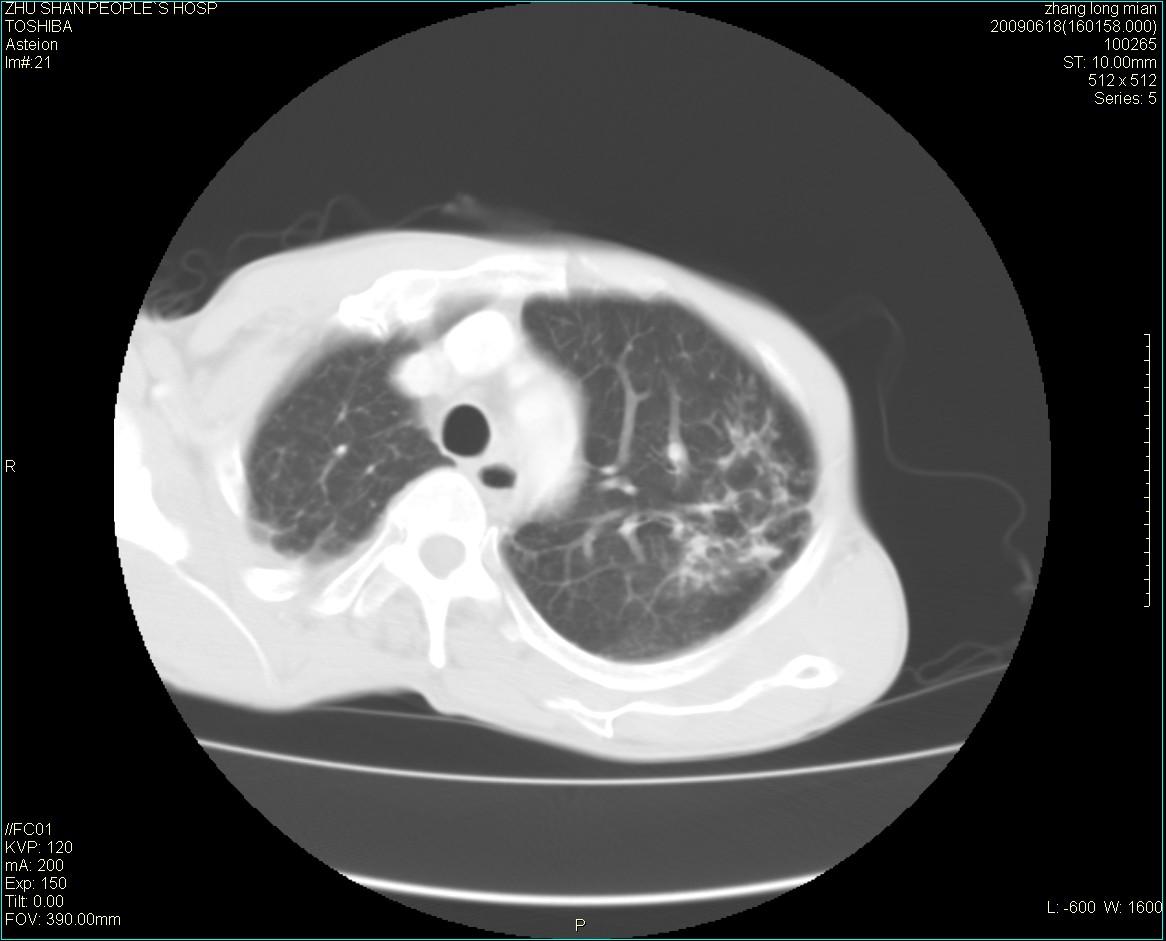

男性 65岁 胸片发现右下肺包块.诊断肺ca并纵隔转移没有问题吧!

两侧胸廓不对称,右侧呈塌陷改变,右肺萎缩。

右下肺见浅分叶状软组织块影,边缘有毛刺,其下部似见不完整偏心空洞影,邻近胸膜凹陷征,并胸腔积液。

增强见纵隔区气管隆突上下及左肺门区肿大淋巴结。左肺感染性病灶。

另见右上肺见一枚小结节影,性质待定。